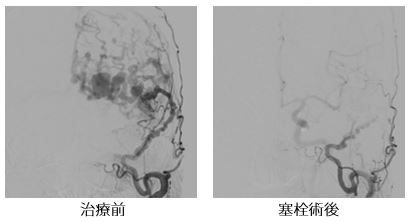

脳動静脈奇形とは、脳の動脈と静脈の間に異常血管網(ナイダス)ができ、脳の動脈の血液がこのナイダスを通って脳の静脈に直接流れ込む病気です。ナイダスの血管は壁が薄くて脆いため、破れると脳出血やくも膜下出血の原因になります。またけいれんや片頭痛で見つかることもあります。治療法は手術による摘出術、血管内治療、放射線治療がありますが、血管内治療単独での根治は難しいため、これらを組み合わせて行います。

脳の表面を覆っている硬膜の中で硬膜を栄養している動脈と本来はつながりのない静脈が直接つながってしまう病気です。硬膜を栄養する動脈と脳の灌流を担う静脈との間に連絡ができてしまうと、脳の静脈圧が上昇することで血流のうっ滞が起こり、脳出血やさまざまな脳機能障害(けいれん、麻痺、言語障害、視力障害、耳なりど)を起こすことがあります。